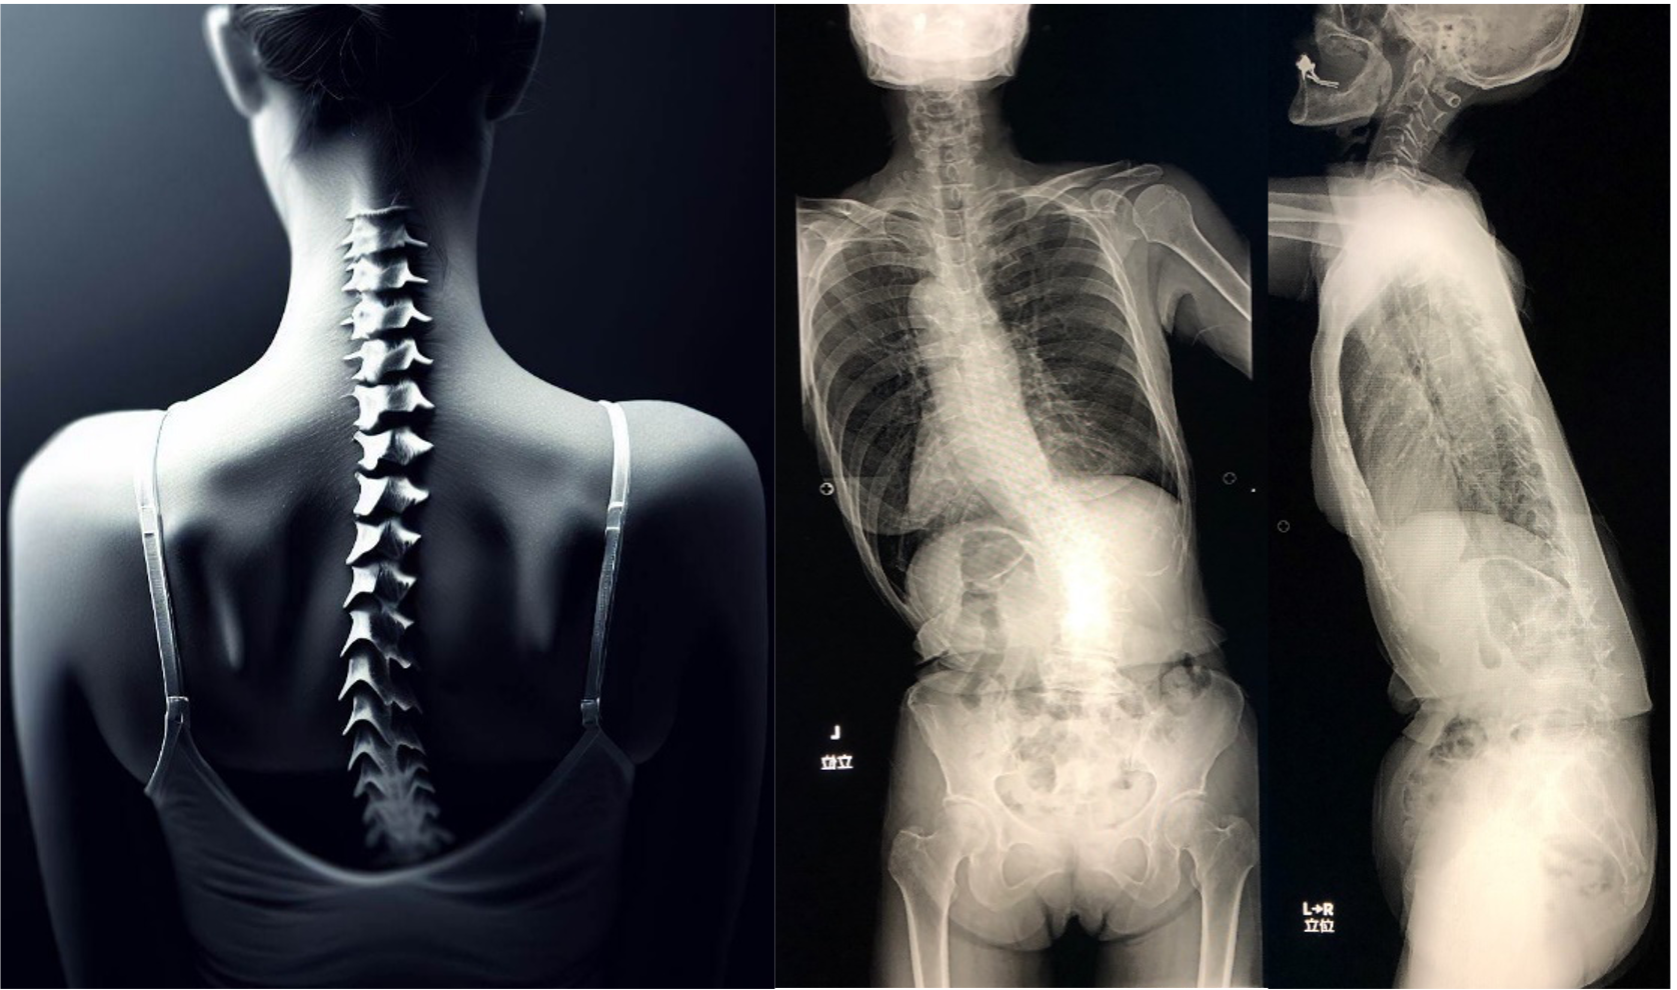

正常な状態の脊柱は、正面から見るとまっすぐに伸び、横から見ると前後にカーブした生理的弯曲をしています。脊柱が横に弯曲したり、前後のカーブの弯曲に異常がみられたりする場合を脊柱変形といい、側そく弯わん症しょう、後こう弯わん症しょう、後こう側そく弯症に分けられます。側弯症は、脊椎自体に原因はない機能性脊柱側弯症と、脊椎自体にねじれや骨の変形がある構築性脊柱側弯症とに分けられます。構築性側弯症とは、正面から見たときに、脊柱が左右に曲がり、脊柱の回旋(ねじれ)を伴う疾患です。その大部分が原因不明の特発性側弯症です。弯曲の程度を評価するには国際基準であるコブ角が用いられ、角度が10°以上ある場合に側弯があると診断されます。日本では思春期側弯症が最も多く、女児に好発します。一般的には成長とともに側弯が変形していきますが、成長が終わると進行も止まることもあります。脊柱が後方に凸状に曲がった状態の後弯症ヒトの脊柱は、横から見たときに、頸椎と腰椎は前に出た状態の前弯で、胸椎は後ろに出た状態の後弯となり、S字状の形をしています。脊柱後弯症は、脊柱が後方に凸状に曲がり、背中や腰が突出している状態のことを指します。加齢が原因となる場合は、骨粗しょう症(P.164 参照)による椎体骨折を伴うことが多く、女性に多く起こります。また、構築性脊柱後弯症の原因には、ショイエルマン病などがあります。